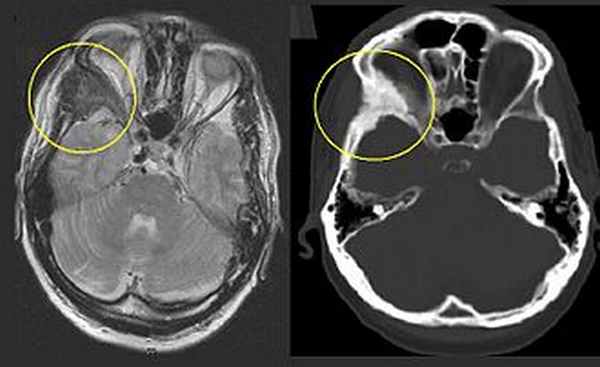

Фиброзная дисплазия справа скуловая кость (осталось). Соответствующие Т2-взвешенные МРТ (слева) и КТ (справа) одного и того же пациента.

Фиброзная дисплазия - это мозаичная болезнь которые могут включать любую часть или комбинацию черепно-лицевых, подмышечных и / или аппендикулярного скелета. [6] Таким образом, тип и тяжесть осложнений зависят от местоположения и степени пораженного скелета. Клинический спектр очень широк: от изолированного бессимптомного моностотического поражения, обнаруженного случайно, до тяжелого инвалидизирующего заболевания, затрагивающего практически весь скелет и приводящего к потере зрения, слуха и / или подвижности.